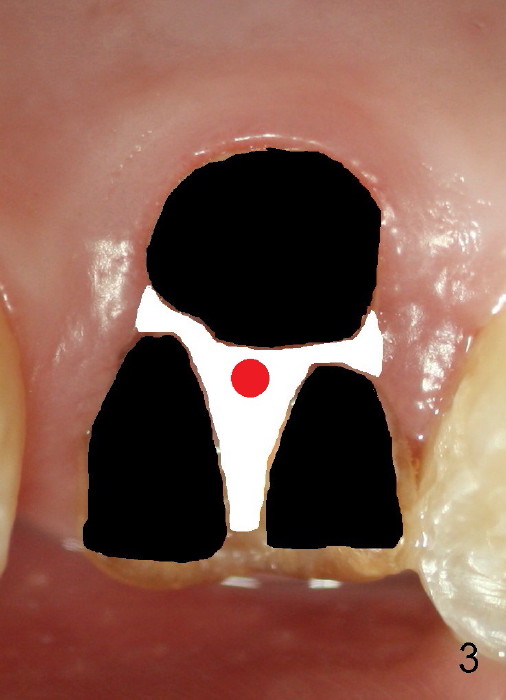

Fig.8 illustrates the implant (blue) placed in the middle of the socket. The remaining buccal and lingual gaps (black) are then closed by graft and membrane. Placing the graft in the deeper portion of the mesiobuccal socket is not so easy because the large implant blocks the entrance (Fig.7 between lower arrowheads). If more graft has been dispensed and the earlier PA shows larger upper space exists (Fig.6 between upper arrowheads), the graft should be placed to that region prior to implant placement.